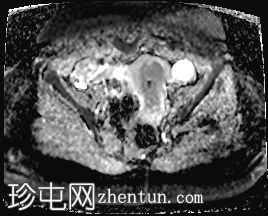

轴位

STIR序列

子宫体积增大,宫底可见息肉样病变,T2加权像呈异常中高信号强度。病变可见轻度扩散受限,增强后呈均匀强化。病变与宫底交界区之间可见一界限清晰的异常高T2信号区域,可能为囊性变性。未见病变超出交界区。

在剖宫产切口远端的前壁上,可见另一处类似的较小病灶。

左侧附件囊性病变,T1加权像信号异常低,T2加权像信号异常高。无增强扫描强化。

子宫内膜息肉是子宫内膜组织的结节状突起。通常表现为T2加权像信号异常高,增强扫描后呈均匀强化。

病理检查通常显示增生期子宫内膜紊乱。